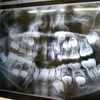

なぜなら、1つ目は「親知らず」を抜いたの!最初は普通の歯科医院にかかったんだけど、親知らずの根っこが神経に近いところにあるらしく、念のため歯科口腔外科を紹介され、総合病院で抜いたよ。ちなみに親知らずは4本生えてて、今回は炎症がよく起こる左下を抜歯することに。麻酔をかけたから抜いた時はそれほど痛くなかったんだけど、ゴリゴリ歯を押す音とか、グイグイ引っ張られる感覚が鳥肌もんでした(-_-;)

そして最後は、キキの矯正。これは2週間に1回のペースで通っているので、同じく木曜の病院の日に組み込んで、全て1日で済ませられるようにしてる。ここの歯科医院もまた私が通ってる総合病院と同じ方面にあるので、ホント助かる~。田舎に住んでると病院にかかるのも一苦労だからね。

肝心の歯並びはかなり良くなって来たんだけど、何せもうすぐフランスへ行くのに、まだまだ矯正は終わりそうもない。6月1日が最後の診察で、フランスへ行ってる間にどうするか指導があると思うんだけど、ちゃんと治るのかな~???

一応、フランスでもマイオブレースを扱ってる歯科医院を紹介してもらって、先生からもそこに連絡してくれるらしい。でもどこまで引継ぎしてもらえるのかはナゾです。。フランスに行ってる間もマイオブレースは引き続きやる必要がありそうだな。